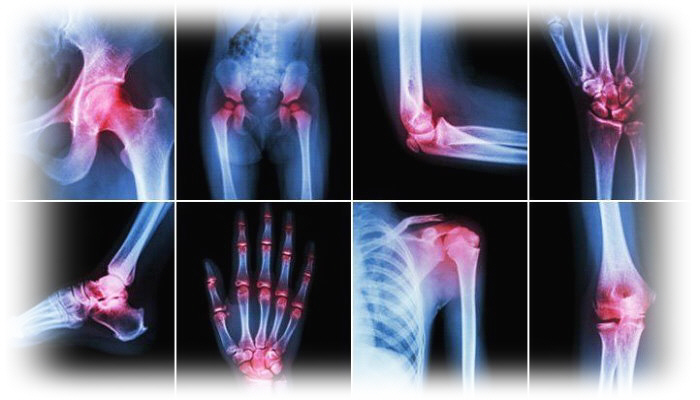

هل تعاني من آلام أو تورم فى أكثر من مفصل فى جسمك بالإضافة إلى ركبتك؟